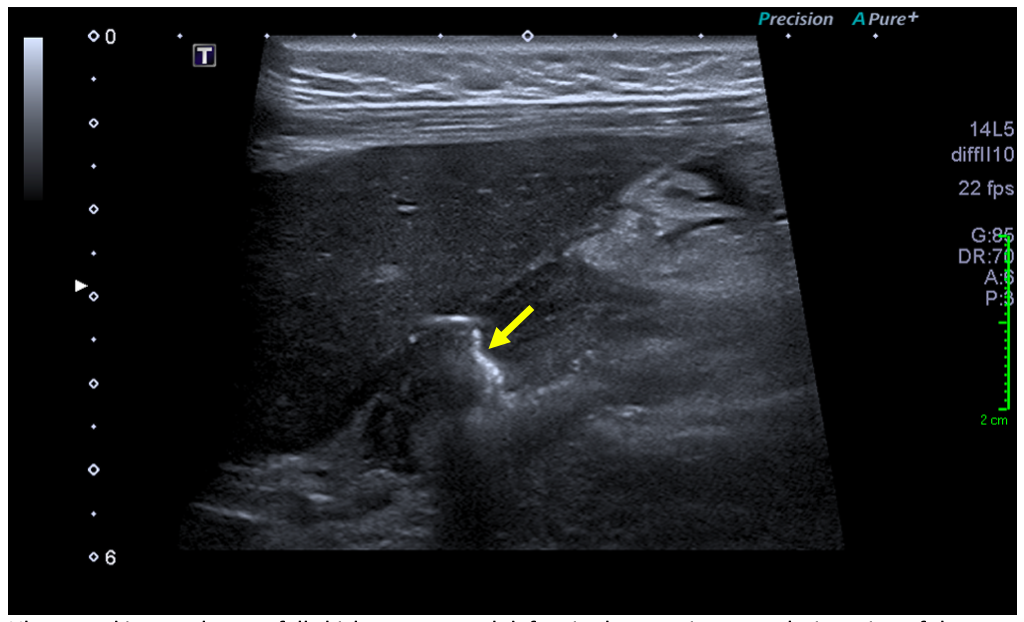

Sonographic examination demonstrated a full thickness mucosal defect of the anterior pre-pyloric region of the stomach, with extraluminal gas locules (see image), trace free fluid in the gallbladder fossa and complex fluid in the right iliac fossa. These features were consistent with a perforated pre-pyloric gastric ulcer. An urgent CT scan was arranged, which confirmed the diagnosis (see images). The patient subsequently underwent emergency laparoscopic surgery. The perforated ulcer, loosely sealed by omentum and the medial edge of the liver, was identified and repaired with an omental plug procedure. Further management included postoperative intravenous antibiotics and PPIs. The patient made a good recovery and was discharged four days post-operatively, with Helicobacter pylori eradication therapy and analgesia.

An active peptic ulcer may be visualised as a localised, asymmetric thickening of the gastric or duodenal wall, with or without echogenic gas in the ulcer crater. A perforated peptic ulcer may be seen directly as a whole-thickness defect, with an echogenic linear track of gas locules originating from the ulcer crater and extending extraluminally into the peritoneal cavity [2, 8].